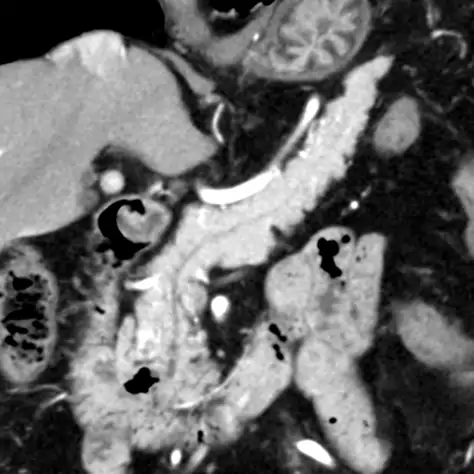

腹部 CT 検査

-

CT による3D 画像

肝臓、胆のう、膵臓を調べる検査